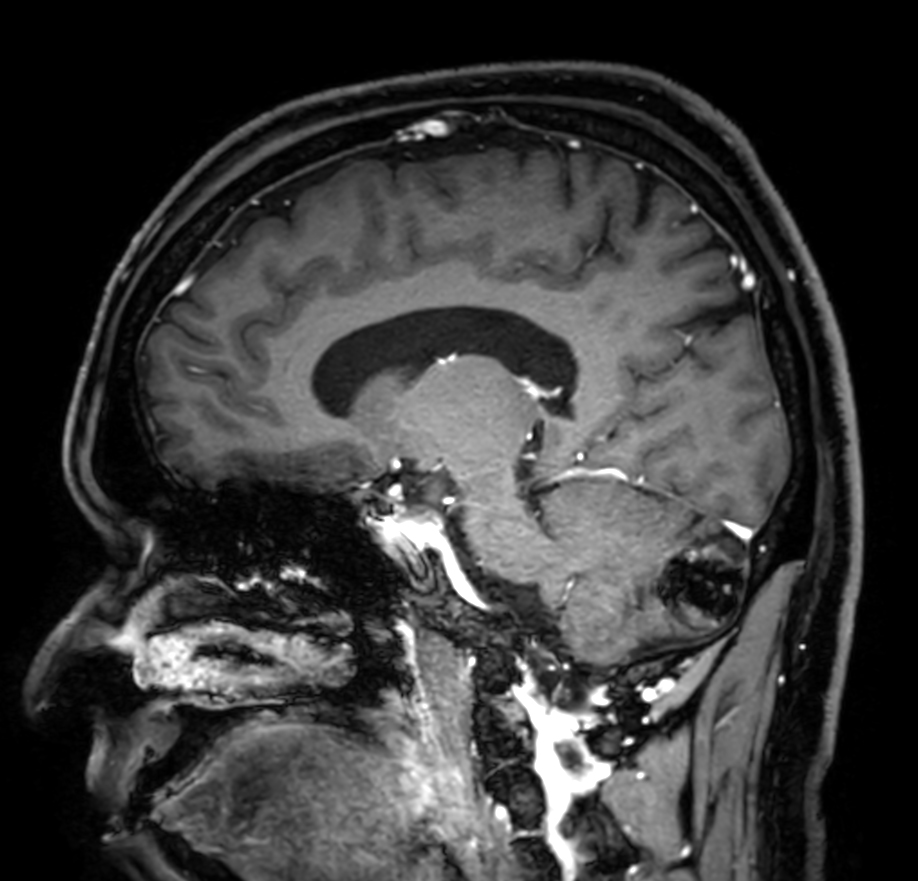

T1w FFE post-gado Compressed SENSE

-

3D T1w FFE FatSat post-gado Compressed SENSE